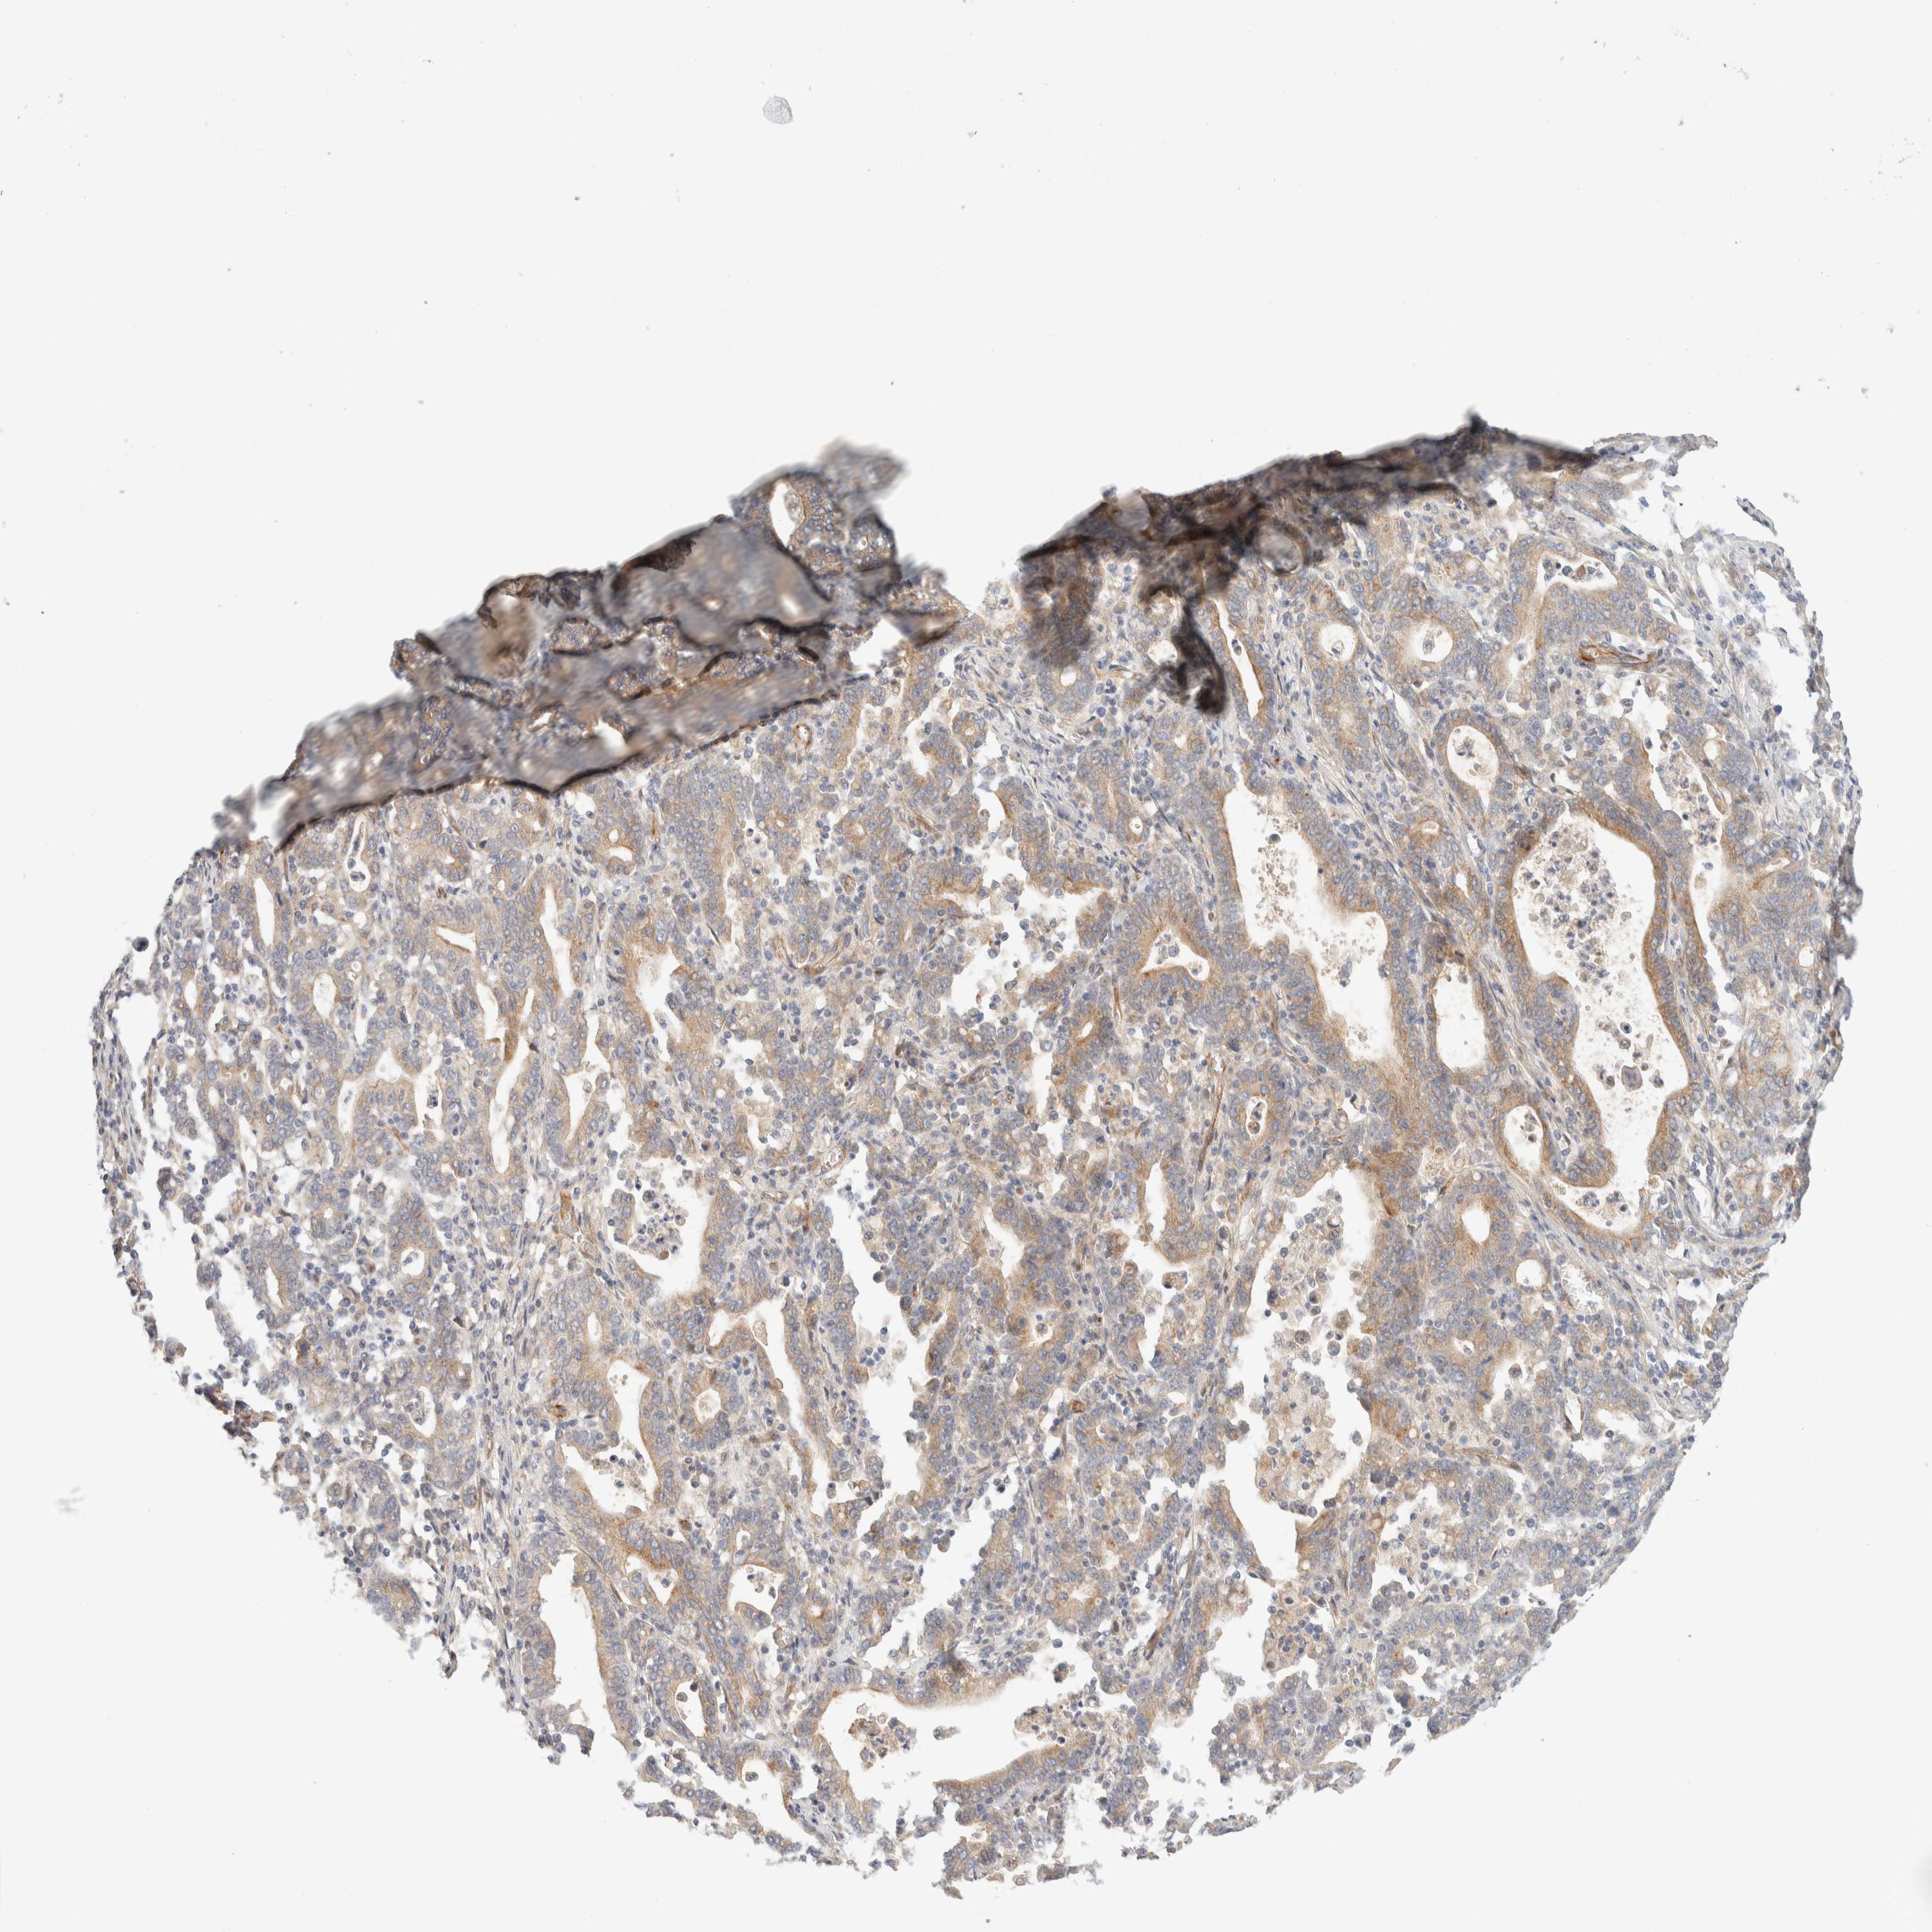

STOMACH CANCER - Protein expressioni

A mouse-over function shows sample information and annotation data. Click on an image to view it in a full screen mode. Samples can be filtered based on level of antibody staining by selecting one or several of the following categories: high, medium, low and not detected. The assay and annotation is described here.

Note that samples used for immunohistochemistry by the Human Protein Atlas do not correspond to samples in the TCGA dataset.

Antibody stainingi

Antibody staining in the annotated cell types in the current human tissue is reported as not detected, low, medium, or high, based on conventional immunohistochemistry profiling in selected tissues. This score is based on the combination of the staining intensity and fraction of stained cells.

Each image is clickable and will lead to virtual microscopy that enables deeper exploration of all samples and also displays staining intensity scores, fraction scores and subcellular localization as well as patient and tissue information for each sample.

Antibody HPA001869

Antibody HPA023882

Staining

High

Medium

Low

Not detected

Intensity

Strong

Moderate

Weak

Negative

Quantity

>75%

75%-25%

<25%

None

Location

Nuclear

Cytoplasmic/membranous

Cytoplasmic/membranous,nuclear

Adenocarcinoma, NOS